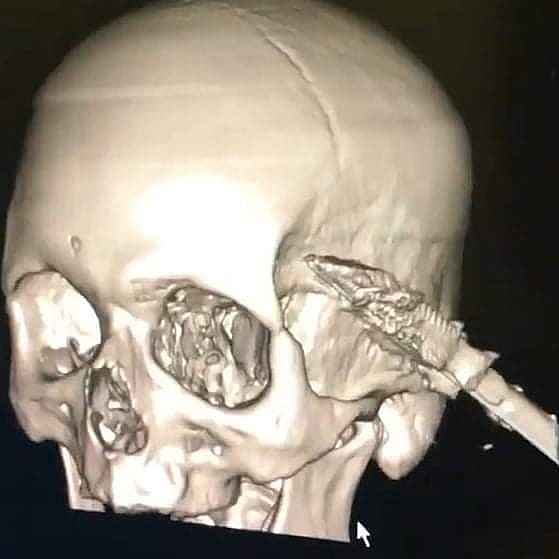

Kastamonu'da uyuduğu sırada koltuktan düşen yaşlı şahsın başına soba maşası saplandı. Maşanın bir kısmı itfaiye ekiplerince kesilirken, kalan kısım ise ameliyatla alındı.

Edinilen bilgiye göre, Araç ilçesinde ikamet eden ve ismi öğrenilemeyen yaşlı şahıs, koltukta uyuduğu sırada düşmesi sonucu kafasına soba maşası saplandı. İhbar üzerine yaralanan yaşlı şahıs, 112 Acil Sağlık ekiplerince Araç Devlet Hastanesine kaldırıldı. Burada ilk müdahalesi yapılan yaşlı şahıs, ardından Kastamonu Devlet Hastanesine sevk edildi. Burada tedavi altına alınan yaşlı şahsın kafasına saplanan soba maşasının bir kısmı, ilk olarak itfaiye ekiplerince kesildi. Ardından kafa tasında kalan kısım ise, yapılan ameliyat ile çıkarıldı. Kafasından soba maşası çıkarılan yaş şahıs, daha sonra servise alınarak tedavisine başlandı.

Edinilen bilgiye göre, Araç ilçesinde ikamet eden ve ismi öğrenilemeyen yaşlı şahıs, koltukta uyuduğu sırada düşmesi sonucu kafasına soba maşası saplandı. İhbar üzerine yaralanan yaşlı şahıs, 112 Acil Sağlık ekiplerince Araç Devlet Hastanesine kaldırıldı. Burada ilk müdahalesi yapılan yaşlı şahıs, ardından Kastamonu Devlet Hastanesine sevk edildi. Burada tedavi altına alınan yaşlı şahsın kafasına saplanan soba maşasının bir kısmı, ilk olarak itfaiye ekiplerince kesildi. Ardından kafa tasında kalan kısım ise, yapılan ameliyat ile çıkarıldı. Kafasından soba maşası çıkarılan yaş şahıs, daha sonra servise alınarak tedavisine başlandı.